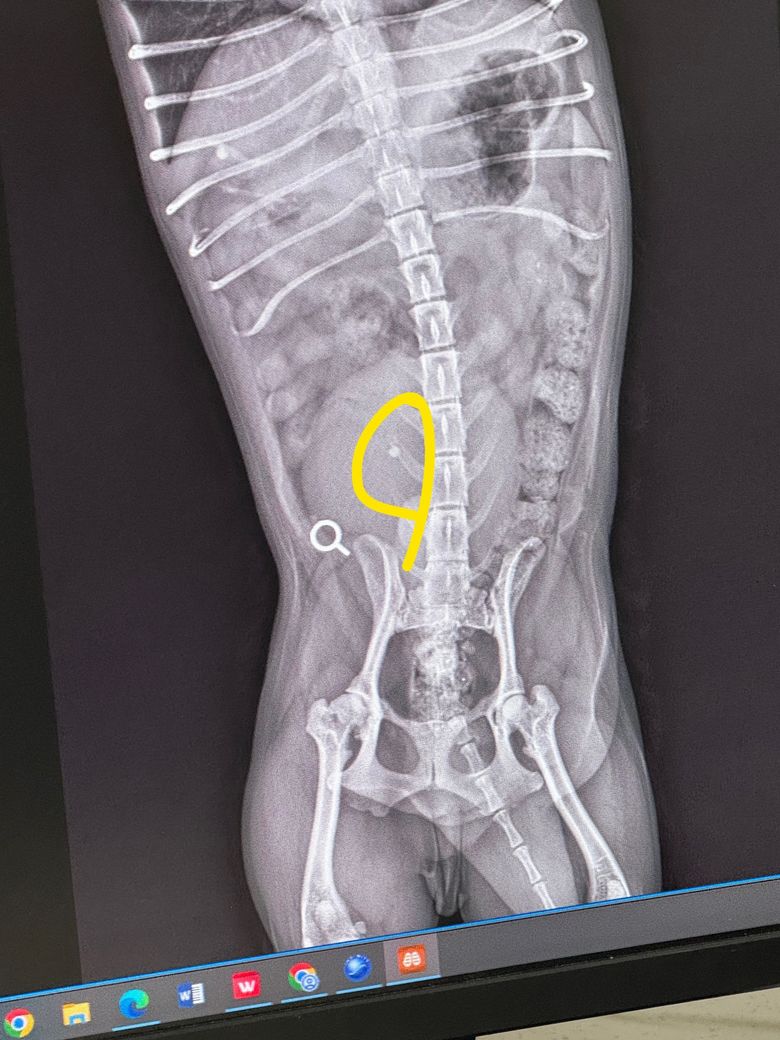

엑스레이 강아지 결석 봐주세요.. 🙏

이번에 병원을 갔다가 엑스레이상 결석이 보이는 것 같다는 이야기를 들었습니다..

결석은 수술로 제거를 해야하나요? 아니면 음수량을 늘려서 경과를 지켜봐야할까요?

결석은 수술적으로 제거하는게 원칙입니다. 결석도 문제지만 우측 고관절 퇴행성 변화가 너무 심합니다. 반바지를 입고 모래가 깔린 시멘트 바닥에서 무릎꿇고 걸어가는 통증과 고통이 있을 수준이니 고관절 관련한 수술도 빠른 시간내에 결정하시기 바랍니다.